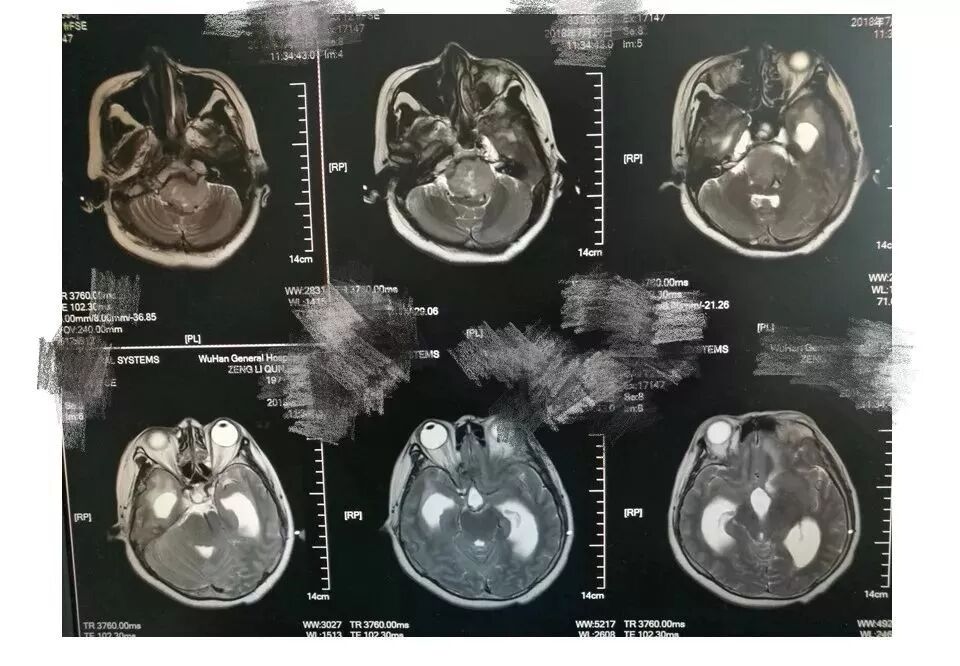

今天为大家分享的是《贝朗时间》第三十八期,由中国人民解放军武汉总医院神经外科副主任姚国杰教授带来的:远外侧入路全斜坡巨大脑膜瘤显微手术1例,欢迎阅读、分享!

远外侧入路全斜坡巨大脑膜瘤显微手术1例